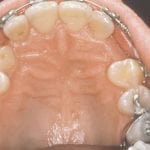

Normally, the maxillary cuspid teeth are the last of the “front” teeth to erupt into place. They usually come into place around age 13 and cause any space left between the upper front teeth to close tighter together. If a cuspid tooth gets impacted, every effort is made to get it to erupt into its proper position. The techniques involved to aid eruption can be applied to any impacted tooth in the upper or lower jaw, but most commonly they are applied to the maxillary cuspid (upper eye) teeth. Sixty percent of these impacted eyeteeth are located on the palatal (roof of the mouth) side of the dental arch. The remaining impacted eye teeth are found in the middle of the supporting bone, but are stuck in an elevated position above the roots of the adjacent teeth, or are out to the facial side of the dental arch.

In cases where the eyeteeth will not erupt spontaneously, the orthodontist and oral surgeon will work together to get these teeth to erupt. Each case must be evaluated on an individual basis, but treatment will usually involve a combined effort between the orthodontist and the oral surgeon. The oral surgeon will expose and bracket the impacted eyetooth.

The goal is to erupt the impacted tooth and not to extract it. Once the tooth has moved into its final position, the gum around it will be evaluated. In some circumstances, there may be some minor “gum surgery” required.